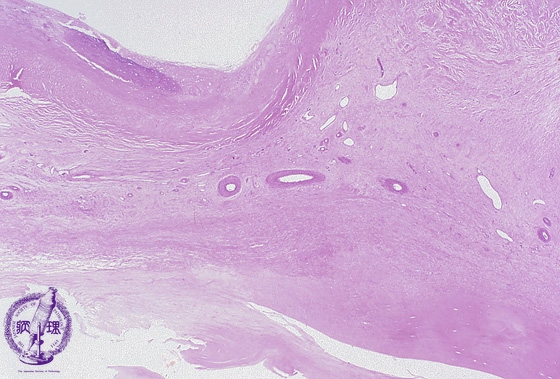

Microscopic image (HE, low power view): The blood vessel is markedly thickened and hyalinized.

Click the image to see the enlarged image.